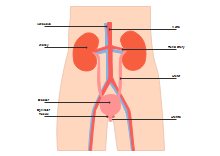

illustrazione scientifica - anatomia umana